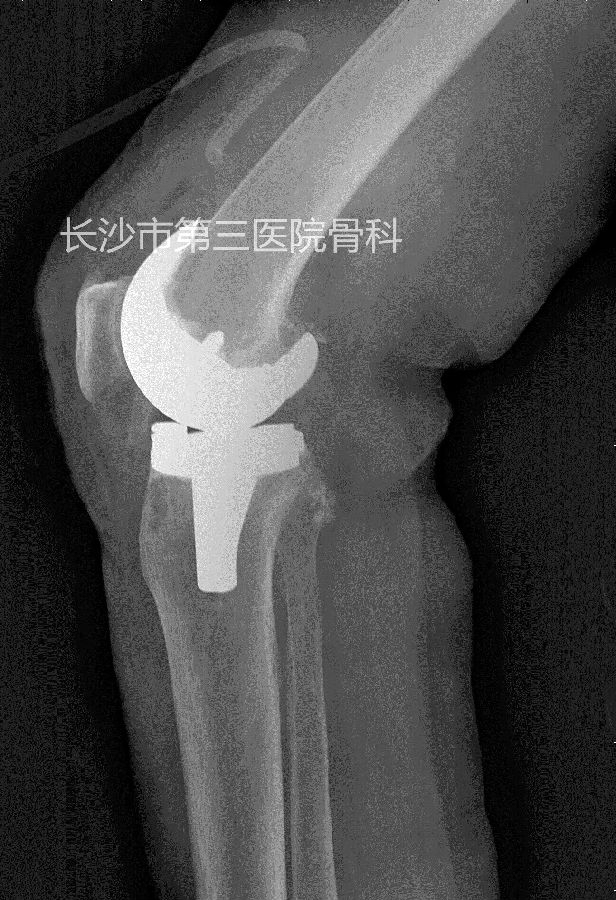

术后影像学资料: